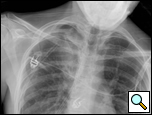

| Figure 4: CT scan showing location of superior segment bleb. |

Patients who have had a previous operation for spontaneous pneumothorax where complete pleurectomy or bleb resection was not performed and who develop a recurrence should be offered re-operation. Prior surgery for pneumothorax is not a contraindication to use of a thoracoscopic approach, as pleural adhesions are relatively few in these patients. A CT scan of the chest readily identifies blebs most commonly seen at the apex of the lung but also in the superior segment of the lower lobe (Figure 4, Video 1 below).